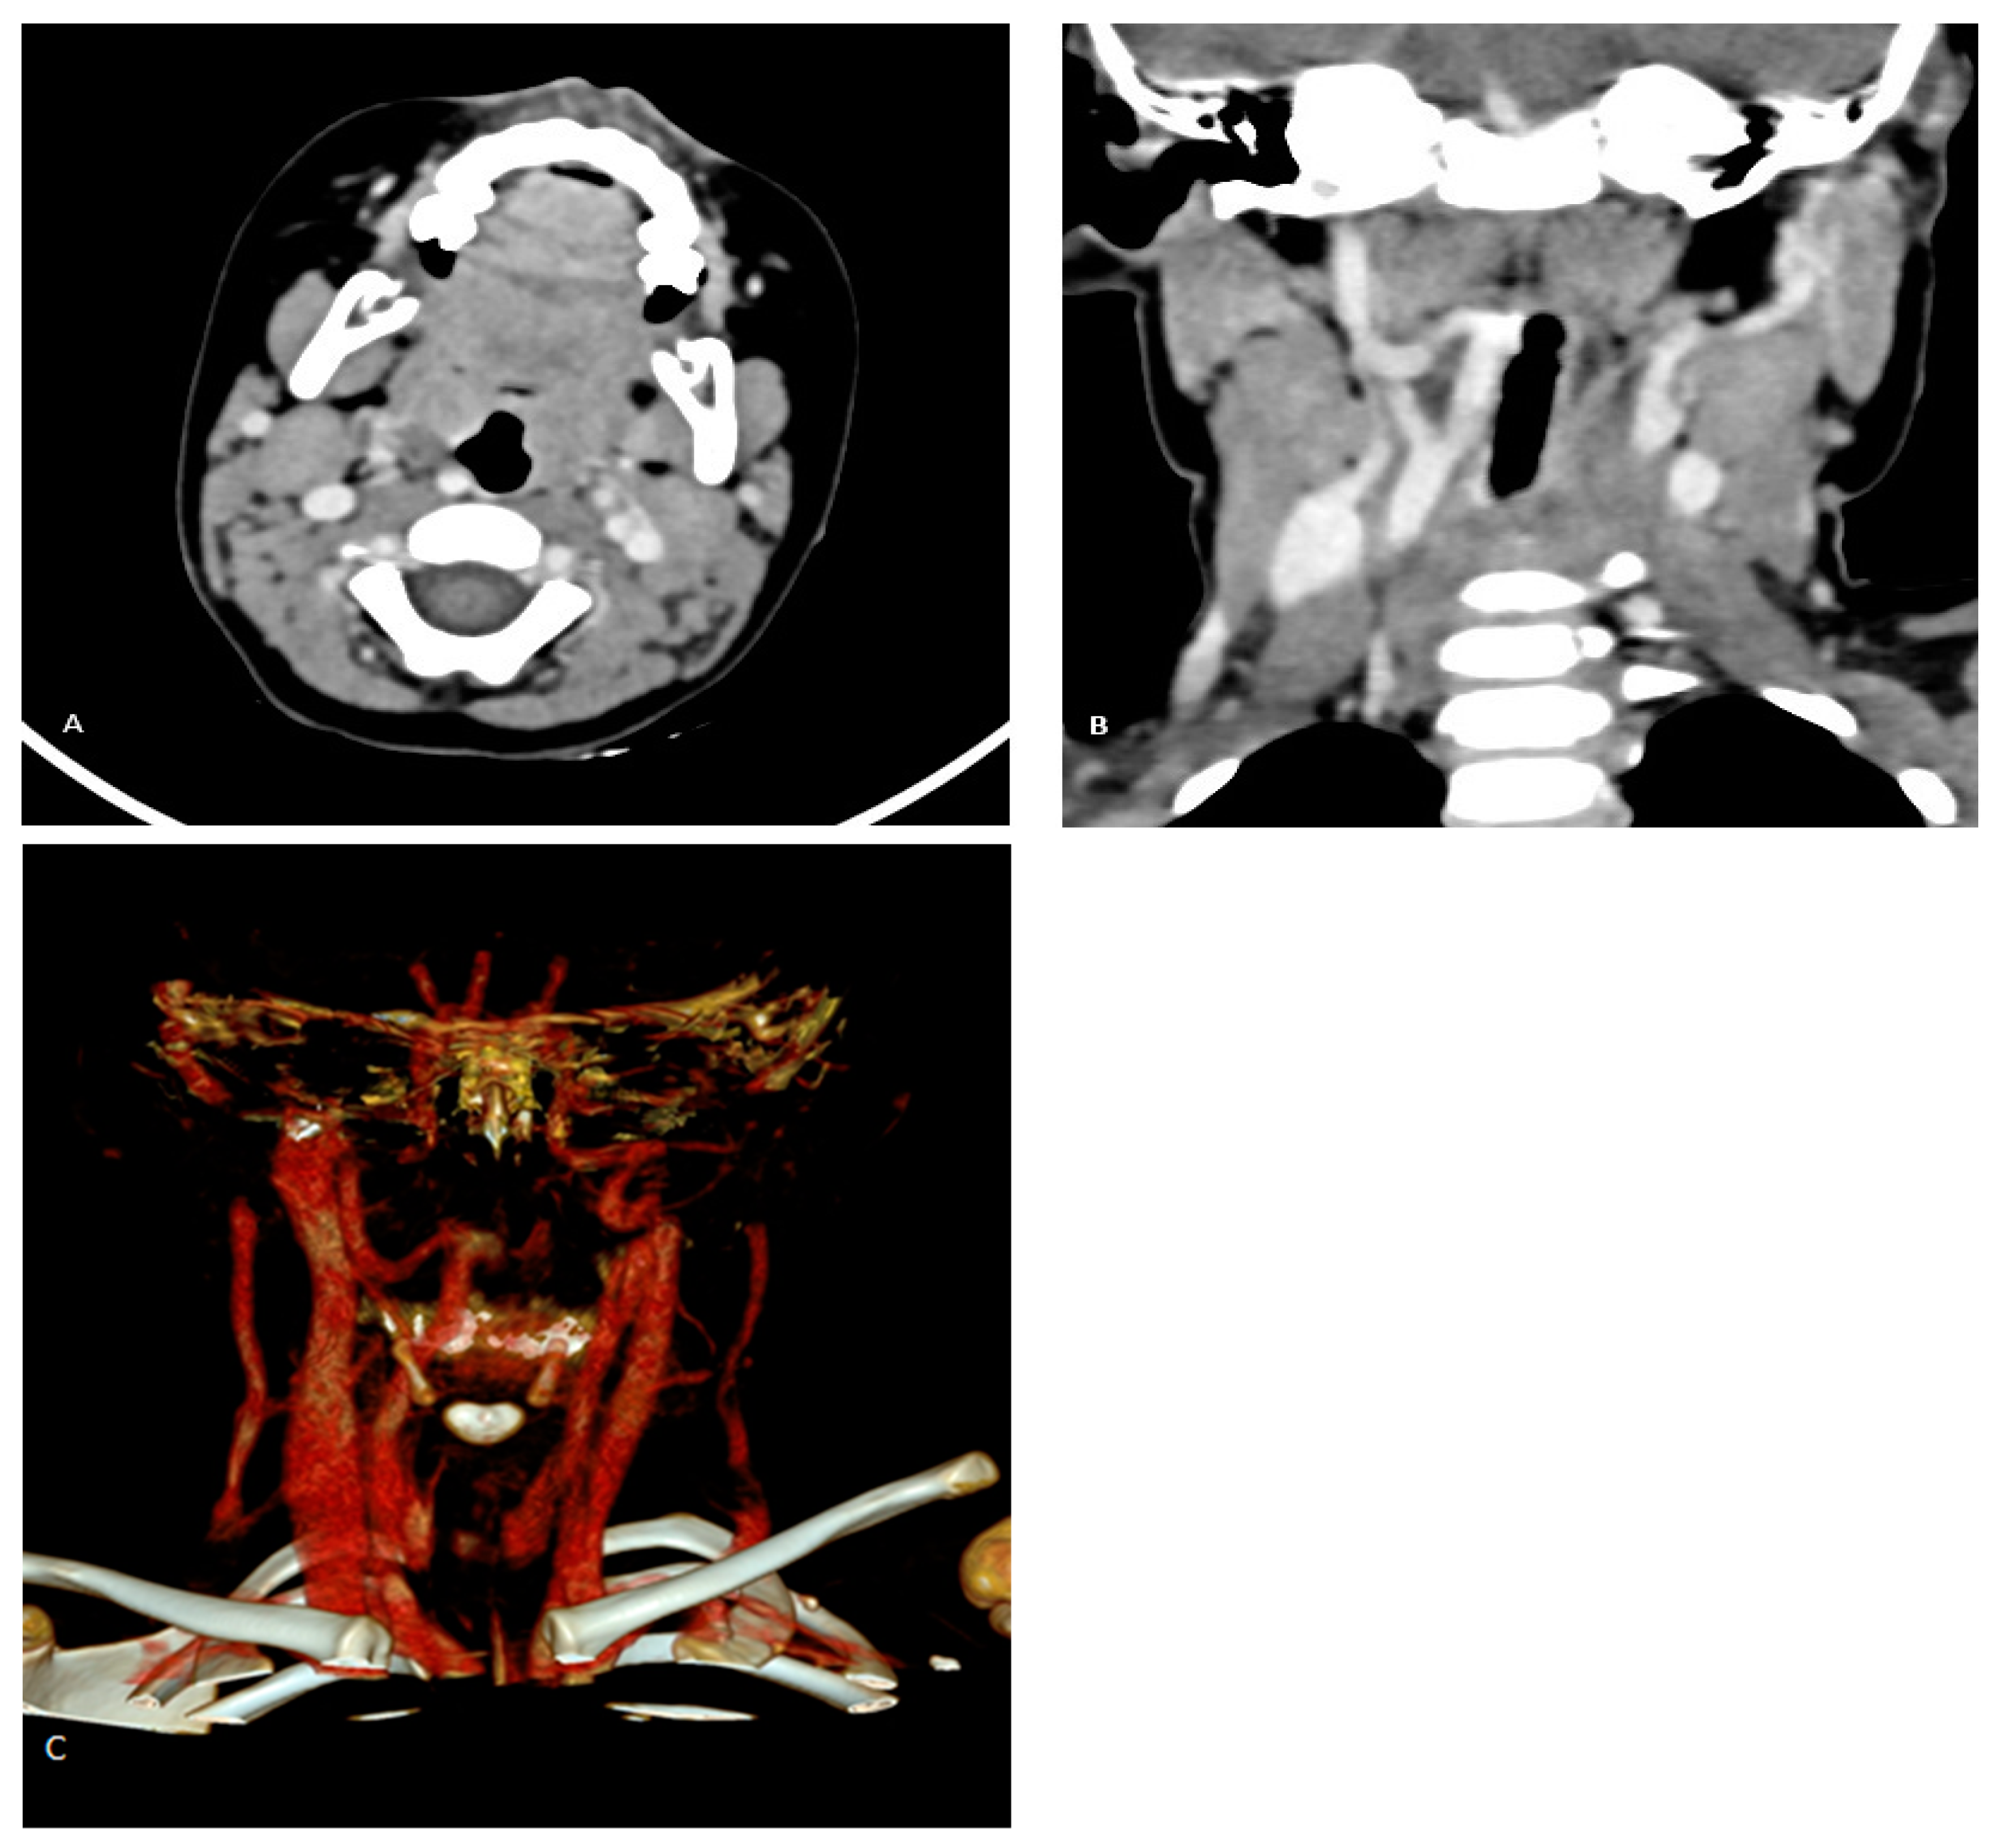

Since the risk of bleeding due to damage to a large blood vessel exceeds the planned benefit of the procedure, further procedure (adenoidectomy) was abandoned with the advice to perform a contrast-enhanced MSCT of the neck to confirm or exclude possible unusual and dangerous position of the internal carotid artery. The MSCT was performed using a 128-slice Siemens Somatom scanner (Munich, Germany). The scan revealed an anomalous medial and retropharyngeal course of the right ICA at the level of the oropharynx. The aberrant vessel was in direct contact with the pharyngeal wall, displacing it (Figure 1). Using the clinicoradiological classification system proposed by Pfeifer and Ridder [7], this case corresponded to a grade IV aberrant ICA.

Figure 1.

(A–C) Right-sided ICA aberration in a 3-year-old child. Axial MSCT scan shows that the right ICA courses retropharyngeally, reaching and displacing the oropharyngeal wall (A). Coronal MSCT reconstruction reveals right ICA tortuosity with kinking and medialization of the vessel (B). Volume rendering displays the course of the right ICA (C).